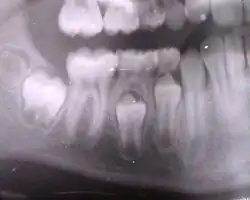

- On voit à la fois des dents temporaires et des dents définitives.

- Radiographie de dents saines (prémolaires, molaires, dent de sagesse incluse) et cariées (2e prémolaire supérieure et 1re molaire supérieure).